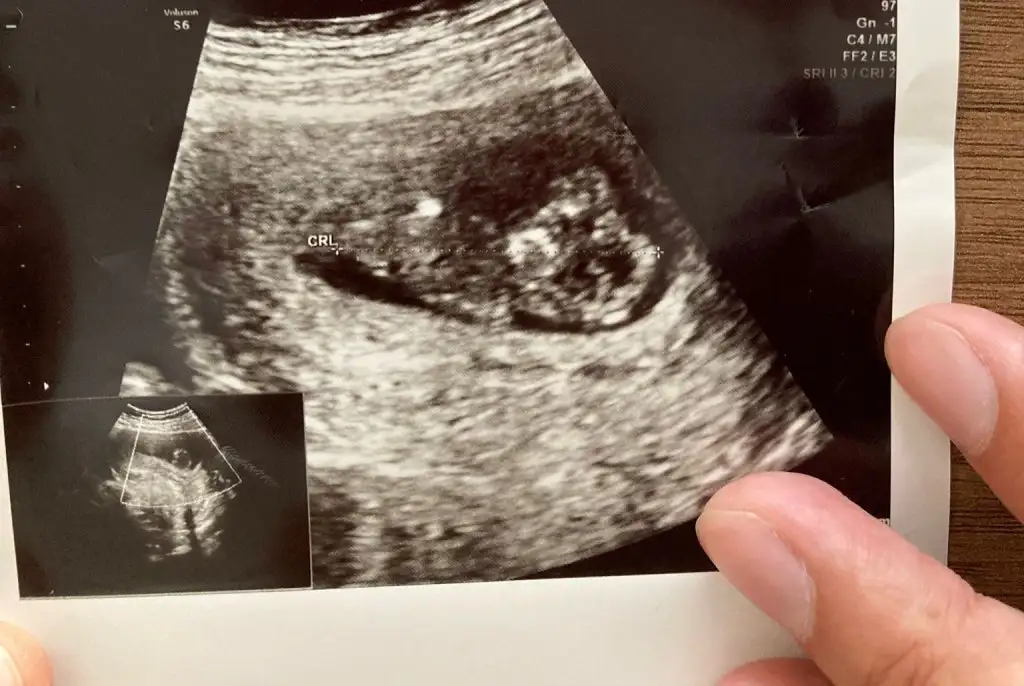

Canm 12 haftadayiz tahminde bulunur musun

• IMG20220801121845.webp

• IMG20220801120709.webp

• IMG20220801120653.webp